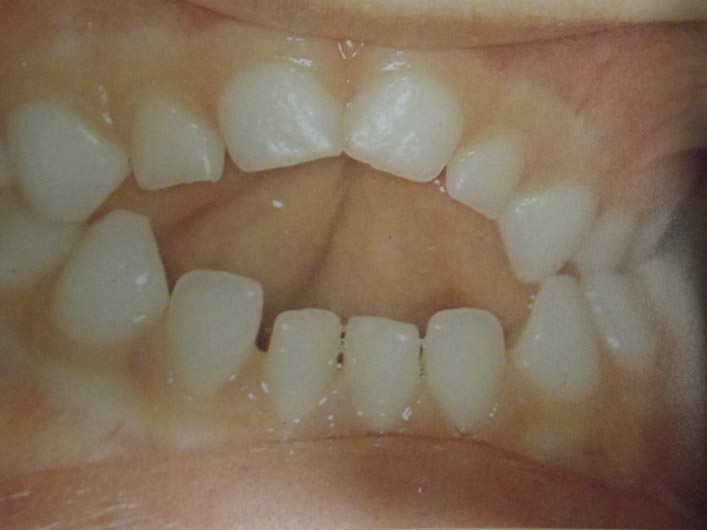

Ανωμαλίες αριθμού, θέσης και σχήματος νεογιλών και μονίμων δοντιών

Υπάρχουν διάφορες καταστάσεις που χρήζουν διάγνωσης και θεραπείας από τον παιδοδοντίατρο. Δείτε τις μία προς μία κάνοντας κλικ στις παρακάτω εικόνες.